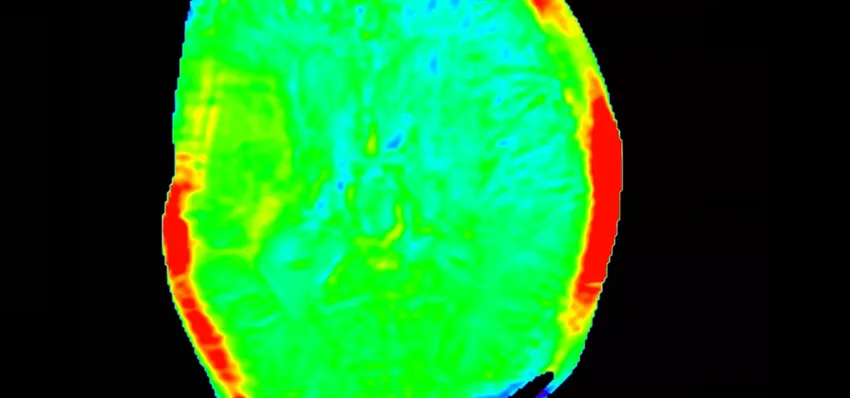

Dementia affects nearly 1 million people in the UK—stealing memories, independence, and time with loved ones. But right here in our community, Cobalt is changing that, by using advanced MRI and PET/CT scans to provide early, accurate diagnosis and also determine the effectiveness of treatment.

Dementia devastates lives—stealing memories, independence, and connections. Despite affecting nearly 1 million people in the UK, the diagnosis is often missed, and research is still underfunded. Cobalt tackles this problem with advanced brain imaging and research that leads to earlier, more accurate diagnoses and better treatments—offering families clarity, support, and hope for a different future.

Cobalt bridges the gap between diagnosis,treatment and the continued search for a cure. Using our cutting-edge MRI technology and the only PET/CT scanner in the 3 counties, we can detect dementia earlier and more accurately—especially in complex cases. Working with the NHS and researchers, we drive new clinical trials and vital discoveries. With your support, we can speed up diagnosis, unlock treatments, and train the specialists shaping the future of dementia care.